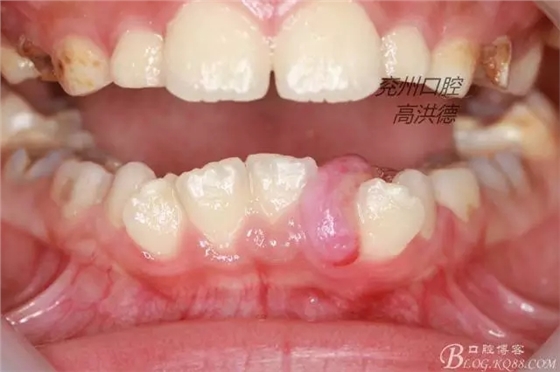

患兒孔xx,性別男,7歲,其母在3月前發(fā)現(xiàn)患兒下頜前牙處有約花生米大小的腫物,曾在其他醫(yī)院就診,建議患兒口服抗生素,不見好轉(zhuǎn),3月來呈漸進(jìn)性生長,來診,孩子正面照。

檢查見;患兒發(fā)育正常,神態(tài)自如,開口度正常,混合牙列,腫物位于31,32之間,32受腫物擠壓影響遠(yuǎn)中傾斜。

診斷:牙齦纖維瘤